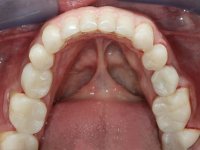

Realizado o diagnóstico e tomada a decisão quanto ao tratamento a executar, tornou-se importante definir qual a sequência de trabalho a adotar no sentido de conseguir a reabilitação da D.V.O. (V.D.O), de forma progressiva e equilibrada. Na primeira fase fez-se uma pré-impressão da arcada inferior com silicone tipo “putty” e em seguida realizou-se o preparo dentário de todo o sector posterior. O preparo para os overlays foi feito coronalmente à linha amelo cementaria no sentido de ser o mais conservador possível. A impressão foi feita com técnica de dupla mistura após afastamento gengival realizado com pasta de caulino. A provisória foi realizada com resina composta de polimerização dual. Em laboratório foram realizados os overlays após se ter aberto ligeiramente (1,5mm) a D.V.O. nos modelos montados em articulador semi-ajustável. Simultaneamente o sector antero-inferior foi encerado no sentido de acompanhar este aumento da D.V.O. Também foi confecionada uma chave de silicone translucido para posterior confeção dos provisórios antero-inferiores. Em boca foi primeiro realizada a provisionalização dos dentes anteriores utilizando resina composta previamente aquecida após preparação das superfícies dentárias para a adesão. Foi colocado o dique de borracha para promover o isolamento absoluto e posteriormente foram colados os overlays. Em laboratório foi realizada nova chave de silicone para confecionar os provisórios antero-superiores. Seguidamente em boca foram preparados os seis dentes antero-superiores após colocação do fio de afastamento gengival. Feita a preparação adequada das superfícies dentárias foi realizada a impressão com técnica de dupla mistura e a respetiva provisória. Em laboratório foram confecionadas 6 facetas feldespáticas num modelo de trabalho tipo “Geller”. A provisória foi removida e as facetas foram coladas em boca utilizando um isolamento relativo competente. Esta opção foi tomada em virtude de uma prévia experiencia negativa com a colocação do dique de borracha na mandibula. Após a colagem dos laminados antero-superiores foram dadas 12 semanas para avaliar a adaptação do paciente à nova situação e então iniciar a confeção das facetas antero-inferiores. Após colocação do fio de afastamento gengival. foram feitos os preparos dentários adequados e em seguida foi feita a impressão. Também foi feita a preparação do dente 3.4 que, entretanto, tinha sofrido uma fratura do overlay. As facetas e a restauração do 3.4 foram realizadas num modelo de trabalho tipo “Geller”. Após remoção da provisória, as facetas foram coladas em boca, utilizando um isolamento relativo pelas razões apontadas anteriormente. Após colocação do trabalho o paciente foi reabilitado por outros colegas com um implante na zona do 2.6 e substituição da coroa aparafusada sobre o implante colocado no local do 3.5. Posteriormente surgiram fraturas nos overlays dos dentes 4.7 e 3.7 que foram reabilitados com overlays em Zr.